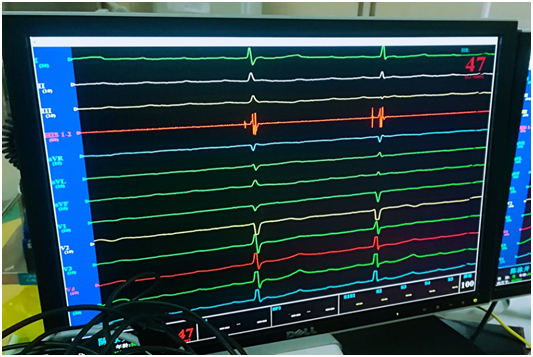

反復(fù)多次嘗試,歷經(jīng)各種挑戰(zhàn),制定相應(yīng)對(duì)策,終于柳暗花明!電極與his點(diǎn)位緊密結(jié)合成革命伉儷,測(cè)試起搏閾值為0.4V,阻抗為460Ω,起搏心電圖如同正常心電圖,參數(shù)非常理想,甚至是超出預(yù)期的理想。

術(shù)后起搏心電圖